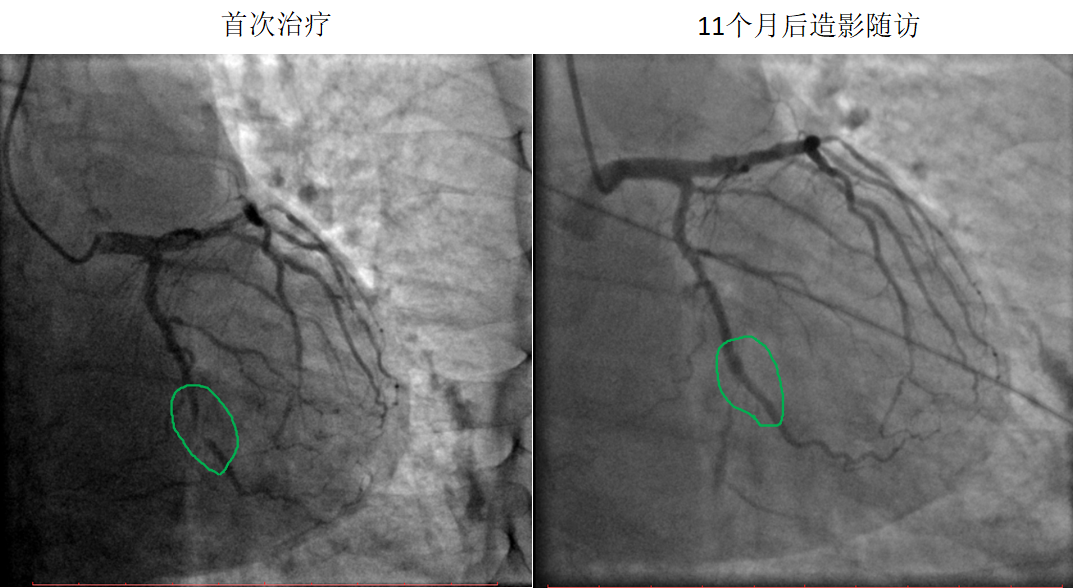

药物球囊治疗闭塞病变

患者:男,51岁

病变部位:LCX中段OM处100%闭塞

使用药物球囊:2.0 x 20 mm

11个月后造影

随访:LCX中段OM发出处通畅